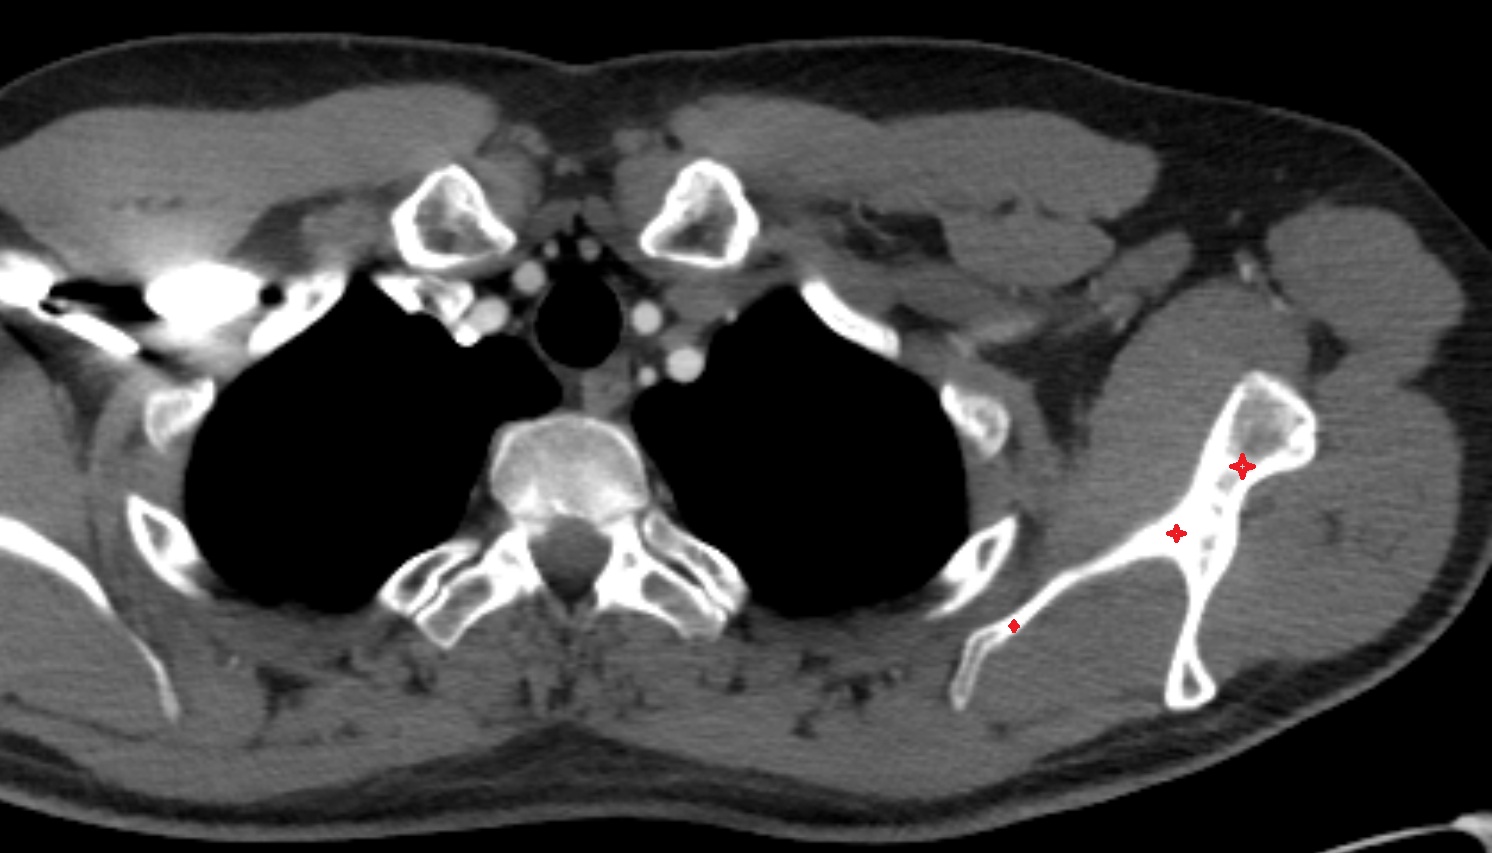

- Sternoclavicular joint

- Clavicle

- Shaft (body) of clavicle

- Acromial end of clavicle

- Sternal end of the clavicle